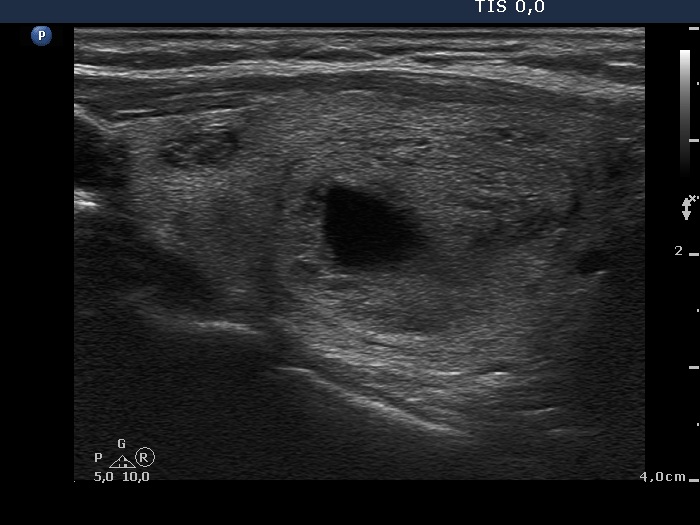

100 consecutive patients with thyroid nodule - Case 35.

(ultrasonographic picture 6)

Left lobe, horizontal scan, color Doppler mode. The left lobe presents non-specific vascularization while the perinodular blood flow of the nodule in the right lobe can be seen well.